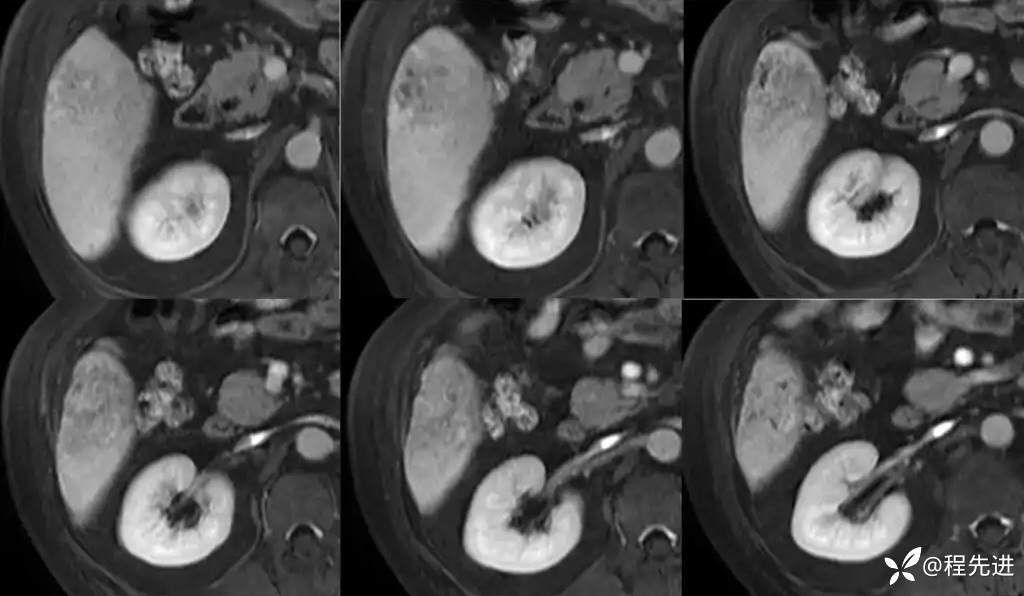

门静脉期:

移行期:

移行期冠状位:

肝胆期: